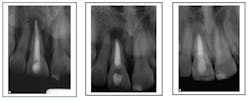

Case corrected with retreatment and root resection surgery (overfill)